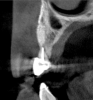

Fig 10. Tomographic images of teeth Nos. 6 (Fig 10), 7 (Fig 11), and 8 (Fig 12) clearly showed vertical gains in alveolar height, including in the edentulous area corresponding to tooth No. 7. The apex of tooth No. 8 was located within the soft tissue because it was force-erupted beyond its socket.

Figure 10

Fig 11. Tomographic images of teeth Nos. 6 (Fig 10), 7 (Fig 11), and 8 (Fig 12) clearly showed vertical gains in alveolar height, including in the edentulous area corresponding to tooth No. 7. The apex of tooth No. 8 was located within the soft tissue because it was force-erupted beyond its socket.

Figure 11

Fig 12. Tomographic images of teeth Nos. 6 (Fig 10), 7 (Fig 11), and 8 (Fig 12) clearly showed vertical gains in alveolar height, including in the edentulous area corresponding to tooth No. 7. The apex of tooth No. 8 was located within the soft tissue because it was force-erupted beyond its socket.

Figure 12

After 3 months of post-orthodontic stabilization, a cone-beam computed tomography scan was taken to re-evaluate the results and plan the future treatment sequence. Tomographic images clearly showed vertical gains in alveolar height, including in the edentulous area corresponding to tooth No. 7 (Figure 10 through Figure 12). The apex of tooth No. 8 was forced-erupted beyond its socket and could be visibly located within the soft tissue.30,33